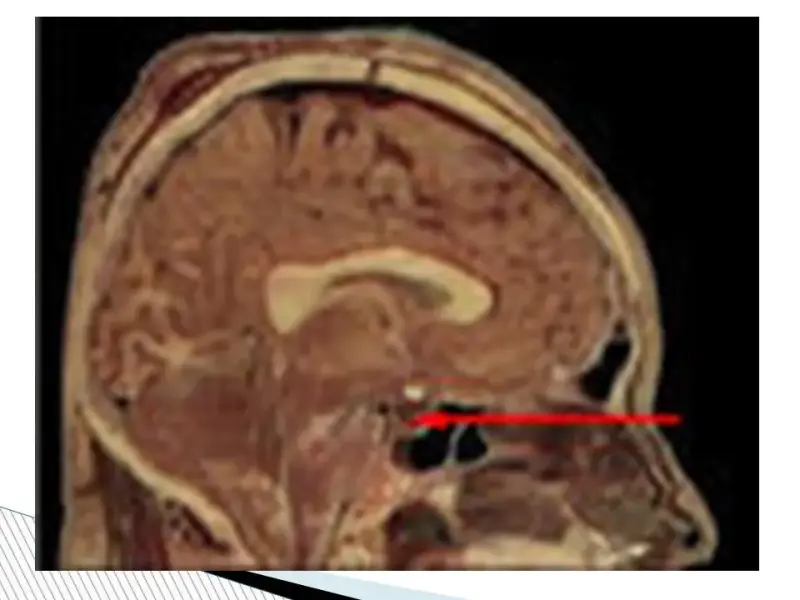

Выработка половых гормонов. В период полового созревания гипофиз, находящийся в основании головного мозга, начинает усиленно вырабатывать вещества, называемые гормонами. Они стимулируют выработку половых гормонов, регулирующих изменения, которые с вами происходят, в том числе влияют на менструацию, и регулирует менструальный цикл. Женские половые гомоны – эстрогены.

Органом регулятором яичников является гипофиз, который находится в головном мозге и синтезирует фолликулостимулирующий (ФСГ) и лютеинизирующий гормоны (ЛГ). В свою очередь, главным органом-мишенью для гормонов яичников, является матка. Другие органы мишени: молочные железы, влагалище, мочевой пузырь, кожа, волосяные фолликулы, кости, сосуды и многие другие. Поэтому недостаток половых гормонов проявляется очень многообразно.